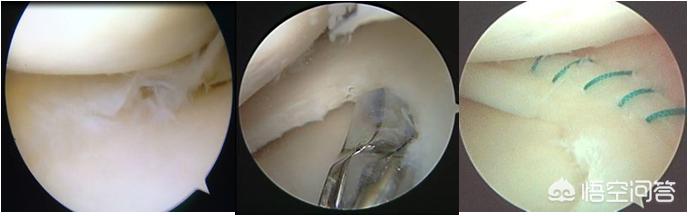

半月板三度损伤图

诊断为半月板损伤并不可怕,半月板损伤虽然为不可逆、不能自愈,但目前采用关节镜微创手术治疗、手术技术成熟,大部分为半月板成形术(部分切除),仅切除损伤部位,尽量多保留正常半月板结构,少数患者选择手术缝合,对于损伤严重无法保留者全部切除,术后合理康复,术后功能可恢复。